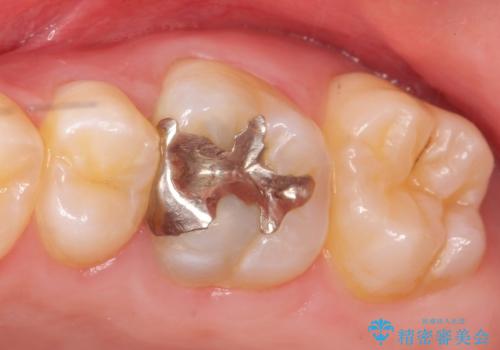

検査の結果左上6に持続痛を認めたため根管治療を行い、症状の緩解を確認後オールセラミッククラウンによる補綴を行いました。

今回用いたオールセラミッククラウンはジルコニアフレームという白い素材の上にセラミックを盛っているため、審美性が非常に高いのが特徴です。

また、ジルコニアは人工ダイヤモンドの材料にも使われているほど高い強度を持っており、そのためオールセラミッククラウンは審美性だけでなく、奥歯やブリッジの補綴も可能とするクラウンです。